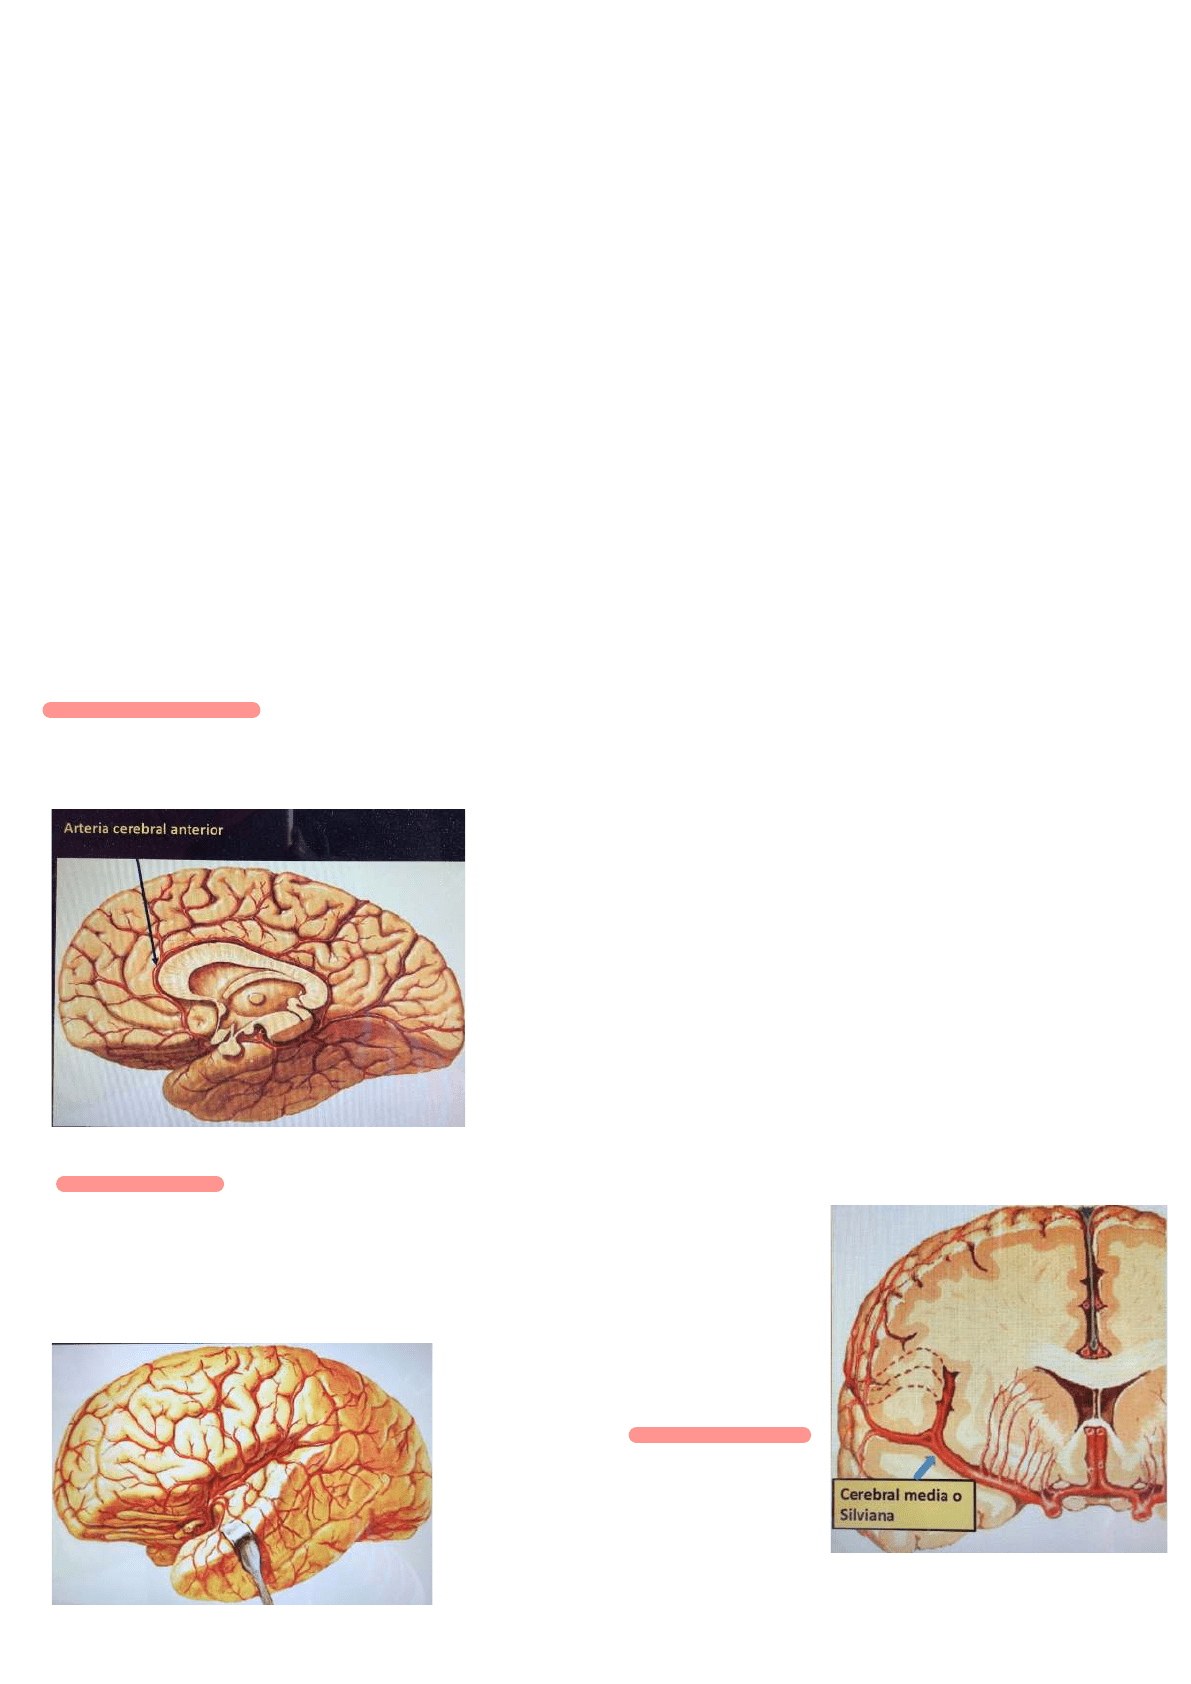

Arterias superficiales

Arterias cerebrales anterior: se genera en la carótida interna, comienza hacia adelante y hacia la cisura longitudinal del cerebro pasando por encima del

nervio óptico. Se aplica a la rodilla del cuerpo calloso y se dirige hacia atrás para terminar como arteria pericallosa.

Da irrigación a la corteza cerebral y el cuerpo calloso. Cara interna del lóbulo frontal y las circunvoluciones frontales ascendentes.

Arteria cerebral media: nace directamente de la carótida interna NO participa en el polígono, penetra en la cisura de Silvio

Sigue le borde inferolateral del hemisferio cerebral y se dirige hacia arriba y atrás cruzando el pliegue

falciforme de la ínsula en donde se divide en dos ramas y sus colaterales. Se aplican a las

circunvoluciones de la ínsula.

Las colaterales que se dirigen hacia arriba se denominan frontoparietales y hacia abajo se denominan

Temporales

La arteria terminal es la arteria del pliegue curvo

que va al lóbulo occipital.

Arteria cerebral posterior: nace de la terminación del tronco basilar a nivel del espacio interpeduncular. Se va hacia atrás pasando por la cara lateral del

pedúnculo cerebral al que contornea y sigue el borde medial del hemisferio y termina en la cara medial en el lóbulo occipital.